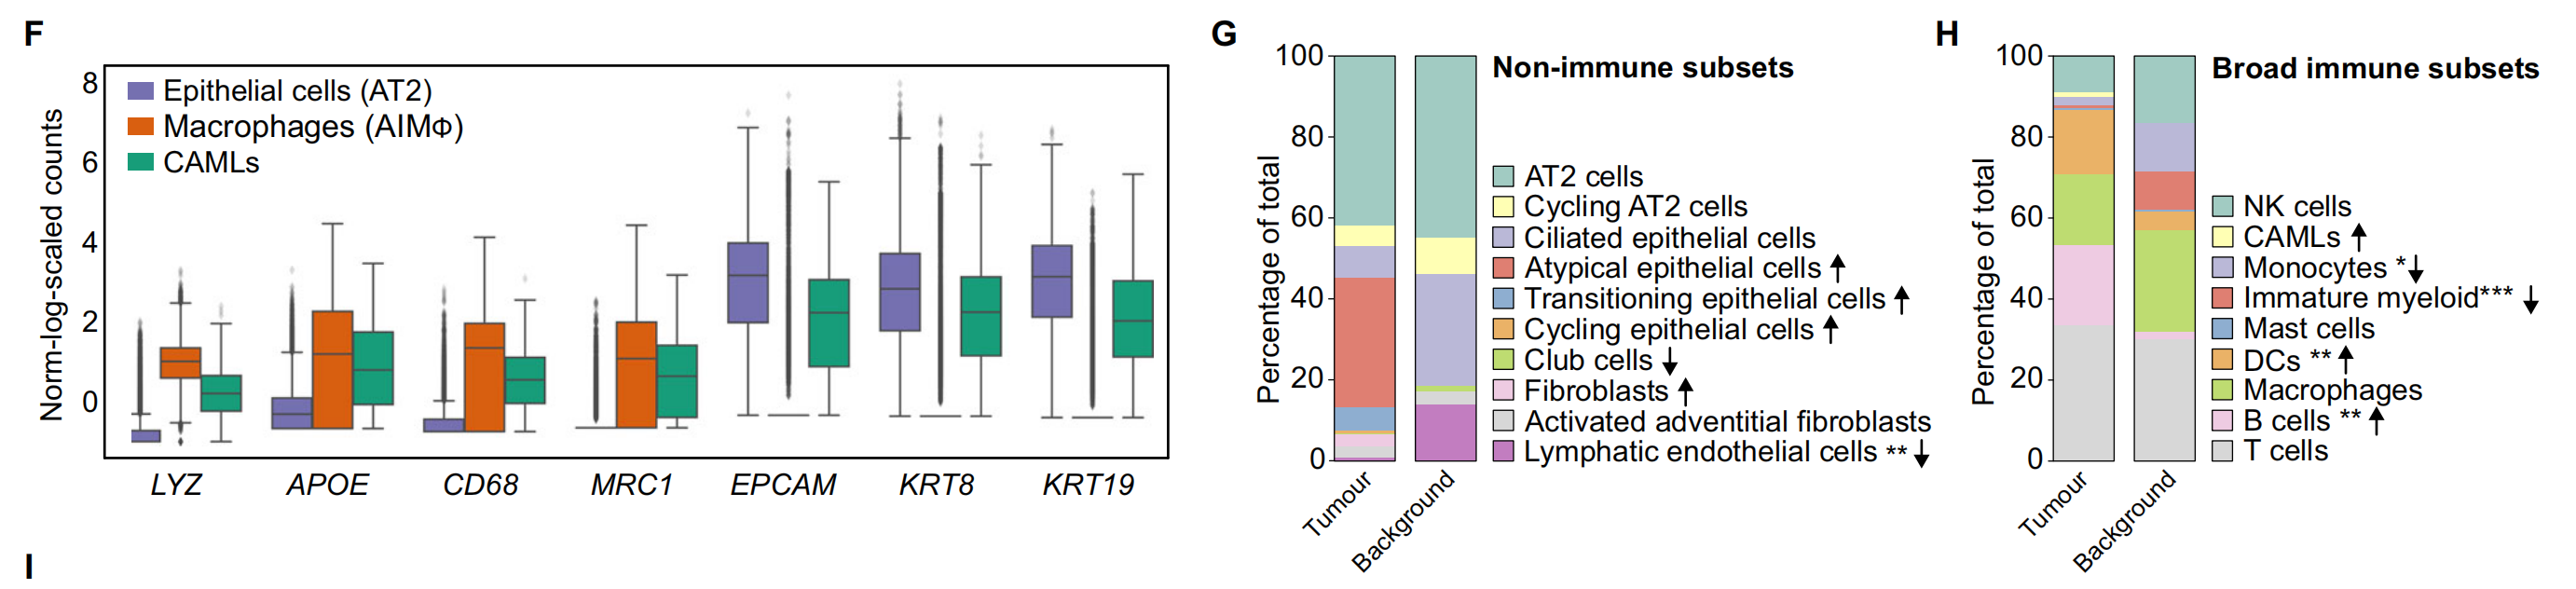

Fig. 1 展示了非小细胞肺癌(NSCLC)异质性的单细胞转录组学分析结果。

以下是对图中各个部分的分析:

E. 等高线图(Contour plot):展示了在AT2细胞(44,399个细胞)、CAMLs(2520个细胞)和AIMφ(16,120个细胞)中共表达的髓系(LYZ, CD68, MRC1)和上皮系(EPCAM)基因。这些数据被标准化、缩放和对数转换。

F. 箱线图(Boxplot):展示了在AT2细胞、CAMLs和AIMφ中髓系(LYZ, APOE, CD68, MRC1)和上皮系(EPCAM, KRT8, KRT19)基因的标准化、缩放和对数转换后的基因表达。箱形图显示了四分位数,须表示1.5倍四分位距。

G. 非免疫细胞亚群的相对比例:在CD235-富集中计算的肿瘤与背景之间的差异。箭头指示了肿瘤与背景相比的增加(↑)或减少(↓)。使用双边Wilcoxon秩和检验和Bonferroni校正进行多重比较。**P < 0.01。没有星号的箭头表示该细胞类型仅在肿瘤或背景中发现。

H. 广泛免疫细胞的相对比例:在所有免疫细胞中识别的CD235-富集中计算的肿瘤与背景之间的差异。箭头指示了肿瘤与背景相比的增加(↑)或减少(↓)。使用双边Wilcoxon秩和检验和Bonferroni校正进行多重比较。*P < 0.05, **P < 0.01, ***P < 0.001。没有星号的箭头表示该细胞类型仅在肿瘤或背景中发现。

I. 肿瘤和背景中NK、DC、B、T细胞和巨噬细胞亚群的相对比例:在CD235-富集中计算的广泛注释内的肿瘤与背景之间的差异。箭头指示了肿瘤与背景相比的增加(↑)或减少(↓)。使用双边Wilcoxon秩和检验和Bonferroni校正进行多重比较。***P < 0.001。没有星号的箭头表示该细胞类型仅在肿瘤或背景中发现。

总体而言,Fig. 1 通过单细胞转录组学和空间转录组学技术,揭示了肿瘤组织与邻近正常组织在不同细胞类型上的异质性和差异。这些结果有助于深入理解肿瘤微环境中细胞的复杂性,并为未来的治疗策略提供潜在的靶点。